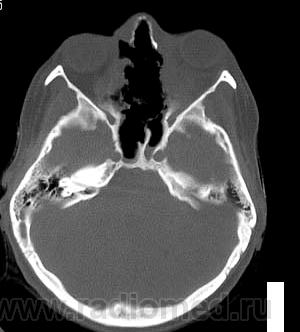

Просьба высказать мнения по поводу представленного патологического процесса.

Кажется, это уже было - гранулематоз Вегенера, если не ошибаюсь.

Гранулематоз Вегенера

Деструктивный процесс в полости носа и в пазухах может представлять собой гранулематоз Вегенера. Требуется тщательное собрание анамнеза, учет клинической картины, и разумеется, биопсия.